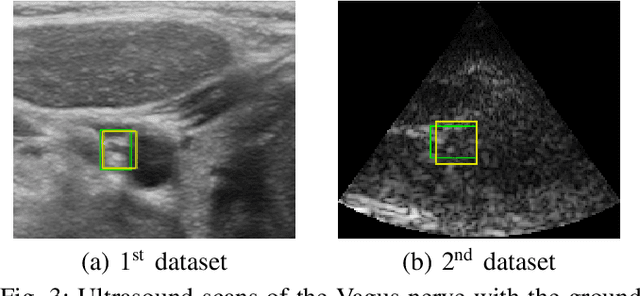

Abstract:Ultrasound scanning is essential in several medical diagnostic and therapeutic applications. It is used to visualize and analyze anatomical features and structures that influence treatment plans. However, it is both labor intensive, and its effectiveness is operator dependent. Real-time accurate and robust automatic detection and tracking of anatomical structures while scanning would significantly impact diagnostic and therapeutic procedures to be consistent and efficient. In this paper, we propose a deep learning framework to automatically detect and track a specific anatomical target structure in ultrasound scans. Our framework is designed to be accurate and robust across subjects and imaging devices, to operate in real-time, and to not require a large training set. It maintains a localization precision and recall higher than 90% when trained on training sets that are as small as 20% in size of the original training set. The framework backbone is a weakly trained segmentation neural network based on U-Net. We tested the framework on two different ultrasound datasets with the aim to detect and track the Vagus nerve, where it outperformed current state-of-the-art real-time object detection networks.